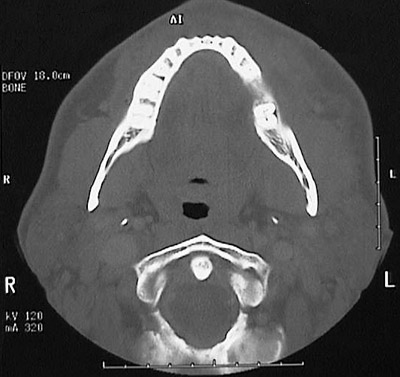

The head CT scan in axial view demonstrates an odontogenic abscess involving the first molar of the left mandible.